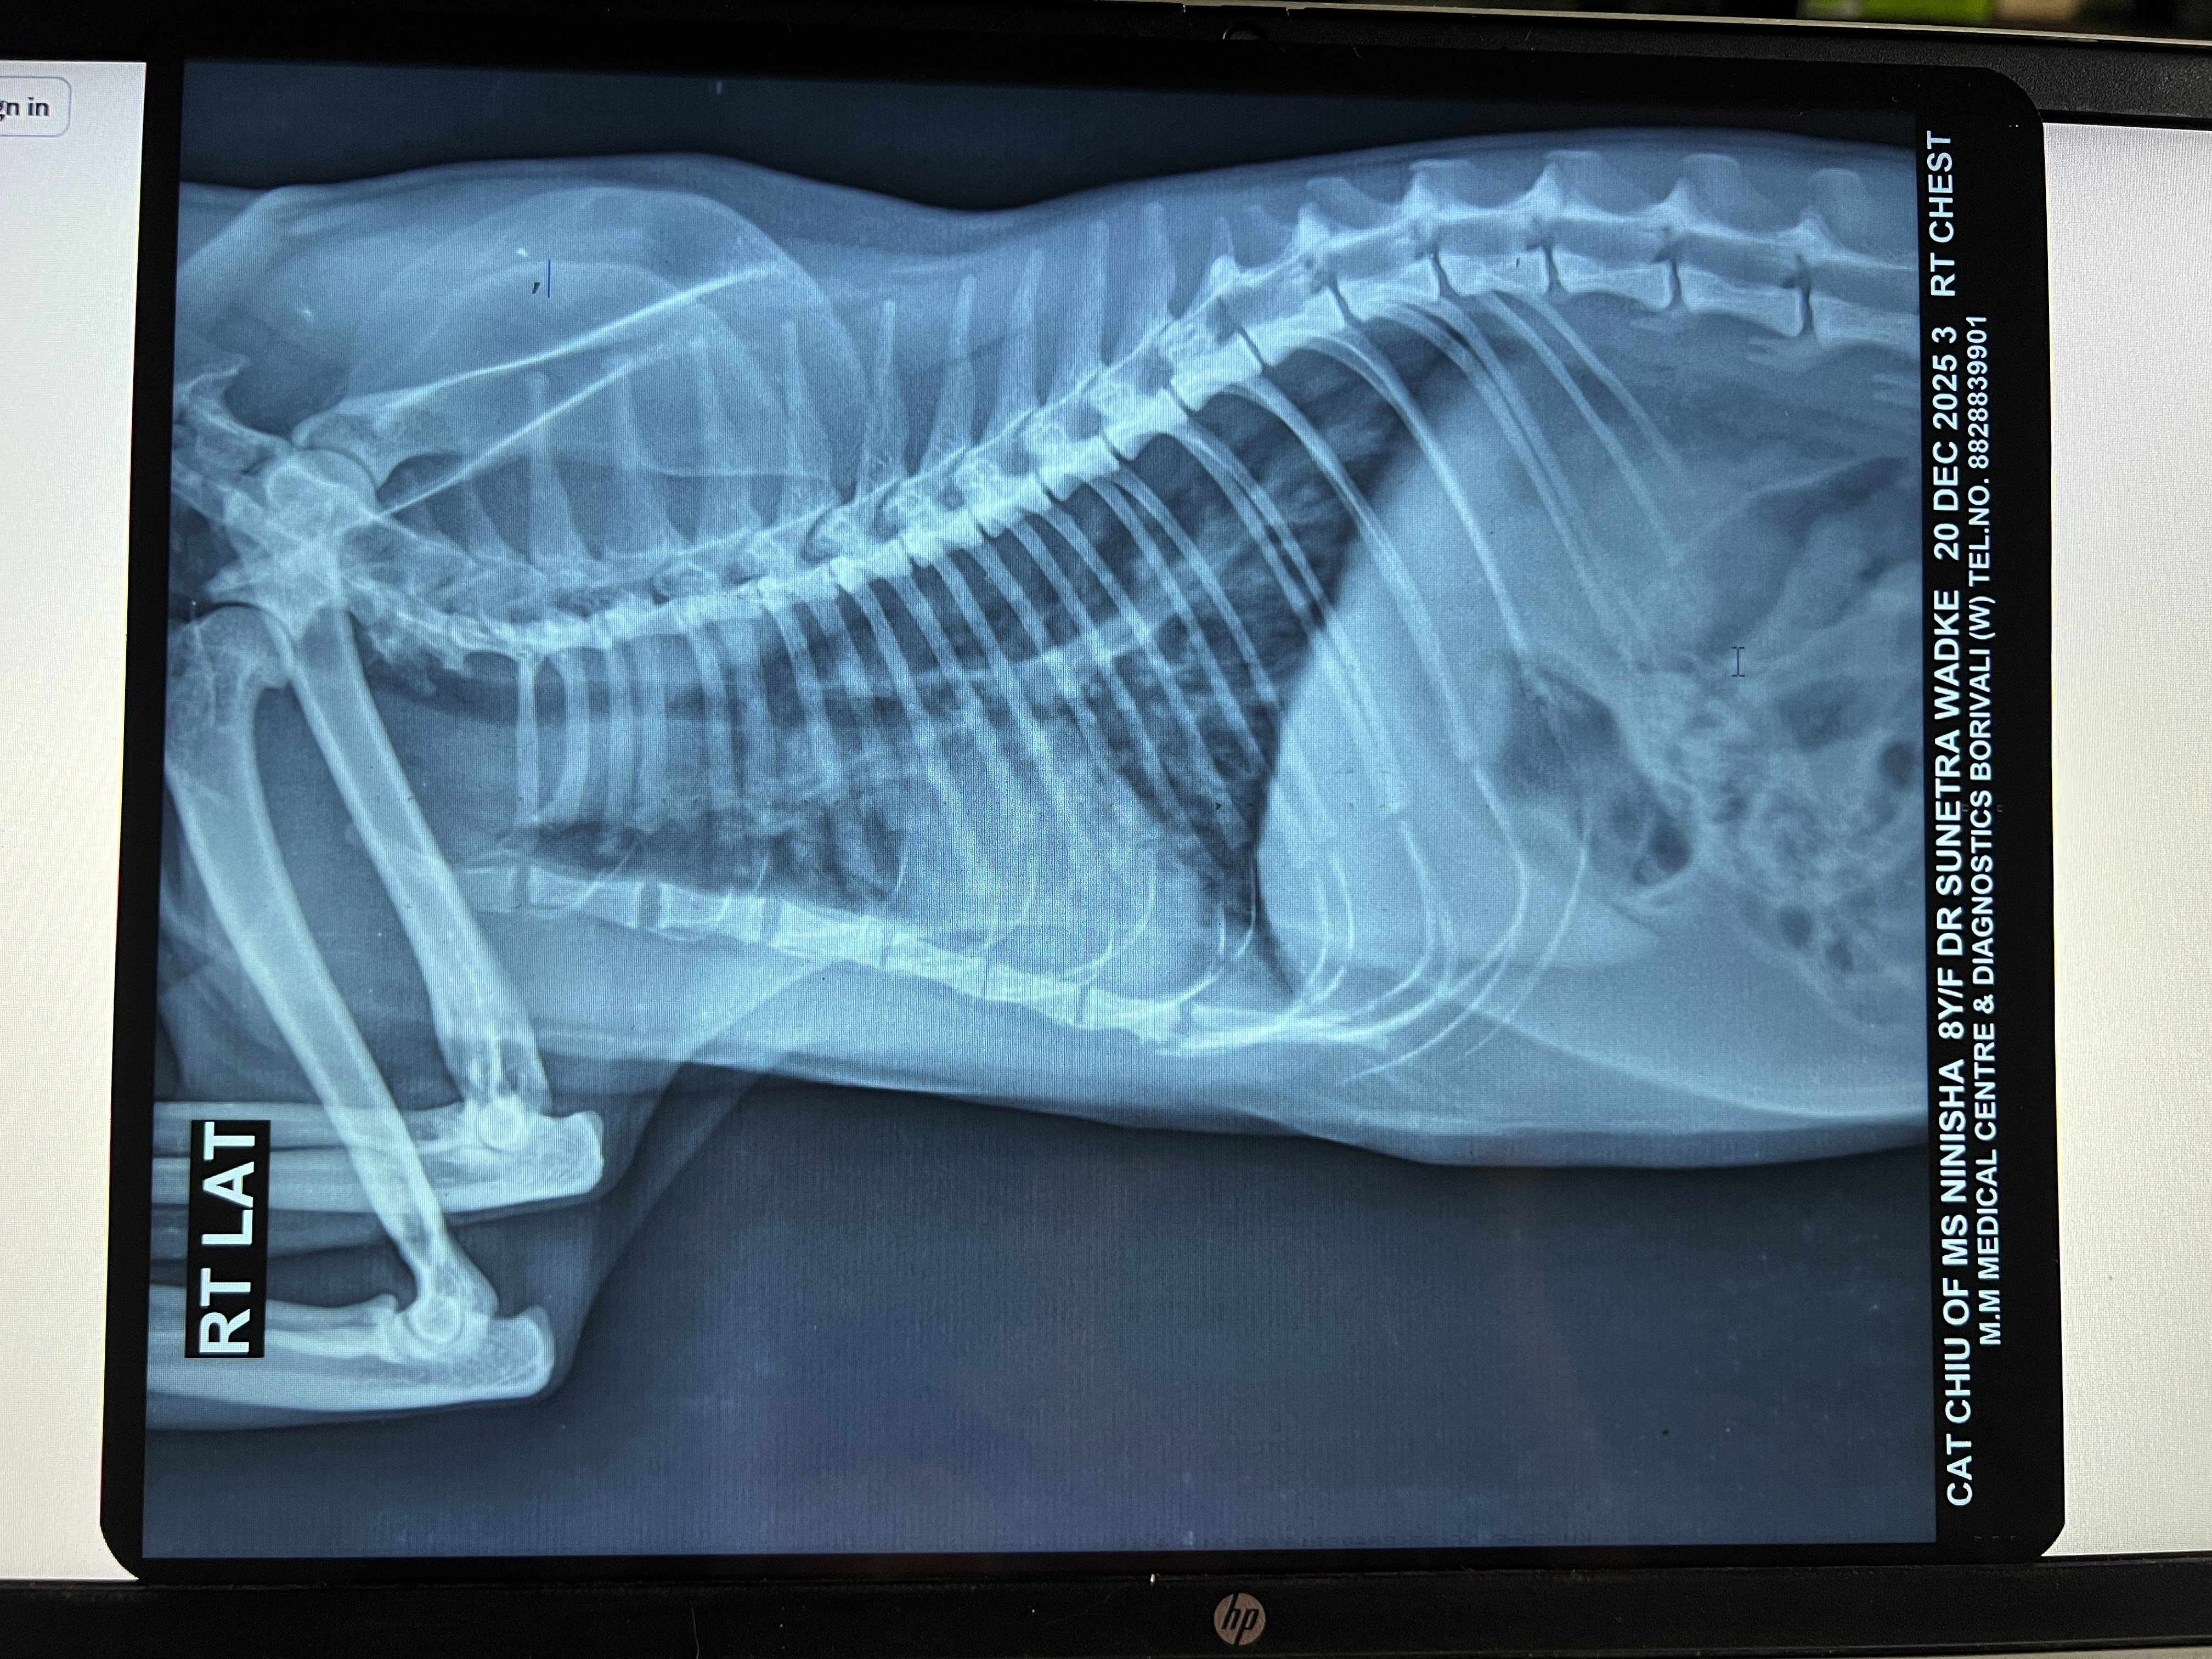

In early August, we got a repeat x-ray (attached) done which still showed bronchial lung pattern. She got Lasix and Penetrat (similar to Frenzyme). She stayed ok for about a month before symptoms returned.

1. Xray - RT LAT - Chiu - 08Aug2025.jpeg1.6 MB · Views: 41 -